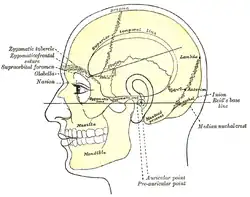

| Side view of head, showing surface relations of bones. (Mastoid process labeled near center.) | |

Mastoiditis is the result of an infection that extends to the air cells of the skull behind the ear. Specifically, it is an inflammation of the mucosal lining of the mastoid antrum and mastoid air cell system inside[1] the mastoid process. The mastoid process is the portion of the temporal bone of the skull that is behind the ear. The mastoid process contains open, air-containing spaces.[2][3] Mastoiditis is usually caused by untreated acute otitis media (middle ear infection) and used to be a leading cause of child mortality. With the development of antibiotics, however, mastoiditis has become quite rare in developed countries where surgical treatment is now much less frequent and more conservative, unlike former times.[2]